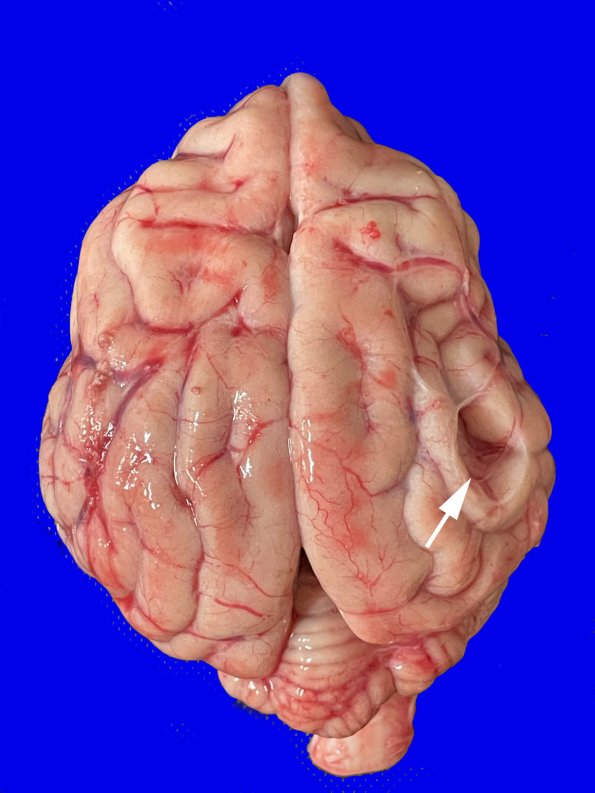

12A1 This arachnoid cyst is shown in an African painted dog (STL ZOO, thanks Dr. Mary Duncan)